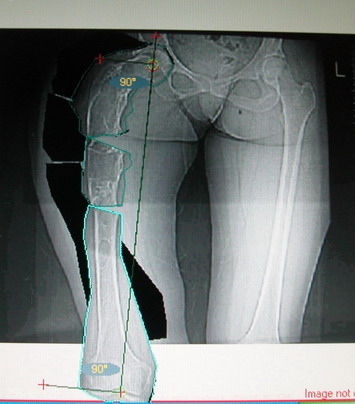

Возможна аппаратная коррекция оси с формированием клиновидного регенерата, которая решила бы и проблему укорочения (что, впрочем, нужно уточнить по схеме, сделанной по рентгенограмме с хорошим захватом смежных суставов - схемка по присланному снимку в приложении). По окончании коррекции - блокируемый стержень, который и сократит время пребывания в аппарате, и вообще возврата к нормальной жизни, а также будет мерой профилактики патологических переломов.

Собственно сустав не беспокоит, объем движений полный. По скиаграммам получается, что достаточно одной остеотомии на вершине деформации, чтобы восстановить длину и вывести коленный сустав в нужное положение.

Т.к. укорочение 7 см, то начинать будем с соеотомии и коррекции аппаратом. Спасибо